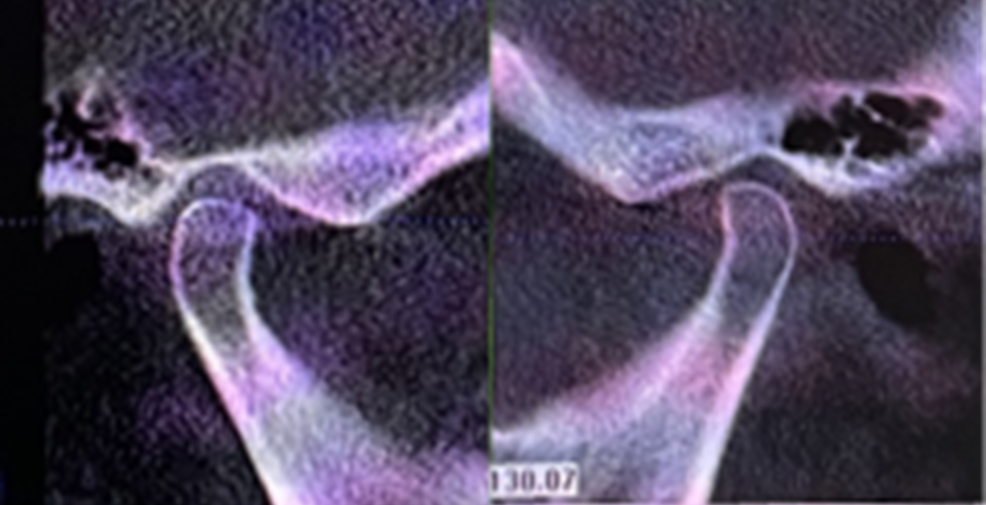

侧貌美学评估:

· 上唇丰满度:过度,鼻唇角80 °(鼻唇角正常范围:90 °-105 °),上下唇超出美学E线,凸面型;

· 头影测量分析,临床诊断为:上颌前突,骨性二类错合畸形,上下中切牙及上下唇前突。

· 侧貌美学预告后,确定了上前牙矢状面前后向的位置关系,中切牙在矢状面上的位置变化:将唇倾的上前牙直立,上中切牙角度减小12度,切端内收8mm。

· 根据正侧貌美学预告,确定了咬合重建最重要的起点,上中切牙三维位置 ,𬌗面参看(FH平面)眶耳平面,并指导全口数字化排牙。